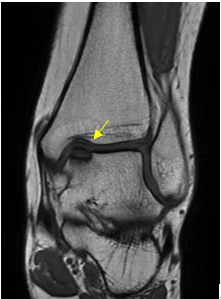

これは距骨骨軟骨障害(離断性骨軟骨炎)といわれるものですが、これは一般的なレントゲン撮影では見えにくいため、MRIやCTなどで確認する必要があります。

MRIで確認される距骨骨軟骨障害(矢印部)